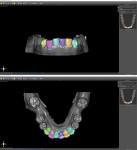

The optically scanned model of the lower arch was opened in the 3D modeling application to evaluate the integrity of the model, trim off any unnecessary data from the border using the cut tools, and repair any flaws using the analysis repair tool. After the model was corrected and smoothed, the teeth were assessed for degree of rotation, alignment, torqueing, and inclination or retraction. To ensure the correct rotation of the teeth, it is best to create "buttons" on the facial aspects of the canines. This facilitates positive seating and helps predict the planned intrusion of the incisors without resulting in unseating of the aligner. The STL file for the newly refined model was then exported to the planning software for aligner design (Figure 10).

Using the STL file, a new project was started in the planning software's orthodontic module. The positions of the teeth were designated to help the software identify each individual tooth and generate approximate margin tracings. Next, the margins of the teeth were refined, and the software segmented each tooth for individual movement (Figure 11). The teeth were then aligned to their final desired positions, and the rate of movement (ie, weekly, bi-weekly, monthly) was selected (Figure 12 and Figure 13). Using known averages of acceptable tooth movement and sequencing, the software then ran its algorithm and determined the sequential steps of alignment for review. Once approved, the software created individual models for each progressive stage of treatment (Figure 14). After identification labels were digitally embossed onto the models and an orthodontic report for the progressive movement of each tooth was exported and attached to the patient's chart, the STL files for each of the models were ready to be exported for 3D printing.